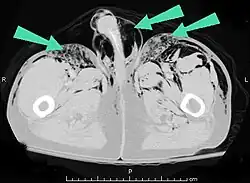

Bolhas de ar no tecido subcutâneo (flecha) tem a sensação de nódulos móveis que se movem facilmente.